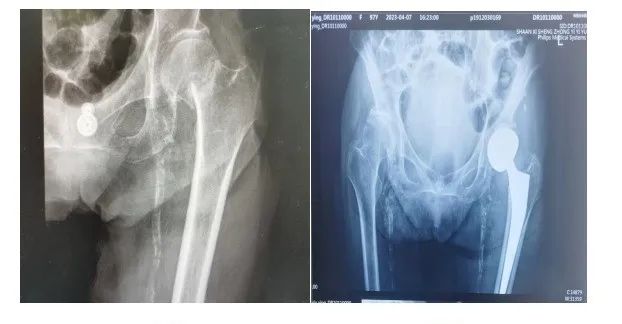

98岁的佟奶奶在自己家里走路时不小心摔了一跤,左髋部坐地受伤不能活动,在家休息后,疼痛未见缓解,由家人送到我科门诊就诊,王彦鹏副主任医师接诊后,完善检查,诊断为左股骨颈骨折。

术前 术后